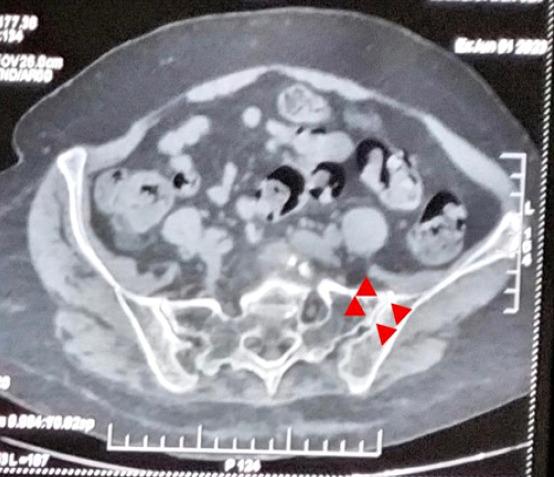

A 60-year-old female patient with grade 2 L5-S1 lytic listhesis initially underwent lumbar interbody fusion to address chronic low back pain and radiculopathy, resulting in significant symptom resolution for a brief period. The patient experienced a resurgence of symptoms within a short duration that proved refractory to conventional medical management and interventional pain management procedures. Ultimately, the patient achieved sustained relief after undergoing endoscopic SIJ ablation.

一名60岁女性患者,患有2级L5-S1溶解性椎体滑脱,最初接受了腰椎椎间融合术以解决慢性腰痛和神经根病,短期内症状得到了显著缓解。患者在短时间内症状复发,事实证明对传统药物治疗和介入性疼痛管理程序均无效。最终,患者在接受内镜下骶髂关节消融术后实现了持续缓解。